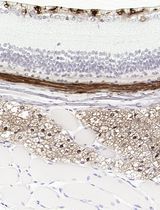

采用 Davidson 固定液和黑色素漂白法优化小鼠眼组织切片的免疫组化染色

Improved Immunohistochemistry of Mouse Eye Sections Using Davidson's Fixative and Melanin Bleaching

Immunohistochemistry (IHC) and immunofluorescence (IF) are fundamental molecular biology techniques to assess protein expression. However, the melanin present normally in the eye in the uveal tract (choroid, iris, and ciliary body) and the retinal pigment epithelium (RPE) poses a significant challenge for IHC and IF. This is because melanin interferes with both chromogenic and fluorescent detection methods. Additionally, formalin fixation, which is commonly used for IHC, can result in shrinkage and loss of cellular detail in the eye. This protocol provides an optimized approach using Davidson’s fixative with a hydrogen peroxide bleaching step to eliminate melanin interference in the mouse eye, improving the quality and interpretability of IHC analyses of the uveal tract and RPE. It is particularly useful for the analysis of uveal melanoma.